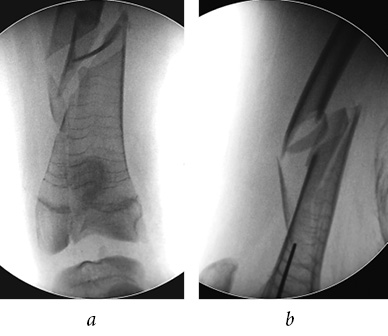

After the standard preoperative examination, surgical treatment was performed on the same day. To eliminate the blockade for the knee joint, the TEN was removed. Due to the pronounced displacement of fragments of the distal third of femur, comminuted nature of the fracture, and delayed consolidation, a mini-invasive osteosynthesis with a metaphysical plate 3.5 LCP was performed to ensure adequate reposition, stable fixation, and preservation of the periosteal blood circulation, (Fig. 8). Additionally, medial TEN shortening of the right femur was performed. After the surgery, the left lower extremity was immobilized with a rear polymer splint from the lower third of the shin to the upper third of the femur for a period of 10 days.

Fig. 8. Intraoperative radiographs of the left femur, mini-invasive osteosynthesis with a metaphysical plate (a); postoperative plain radiograph of the femurs in the frontal view (b)